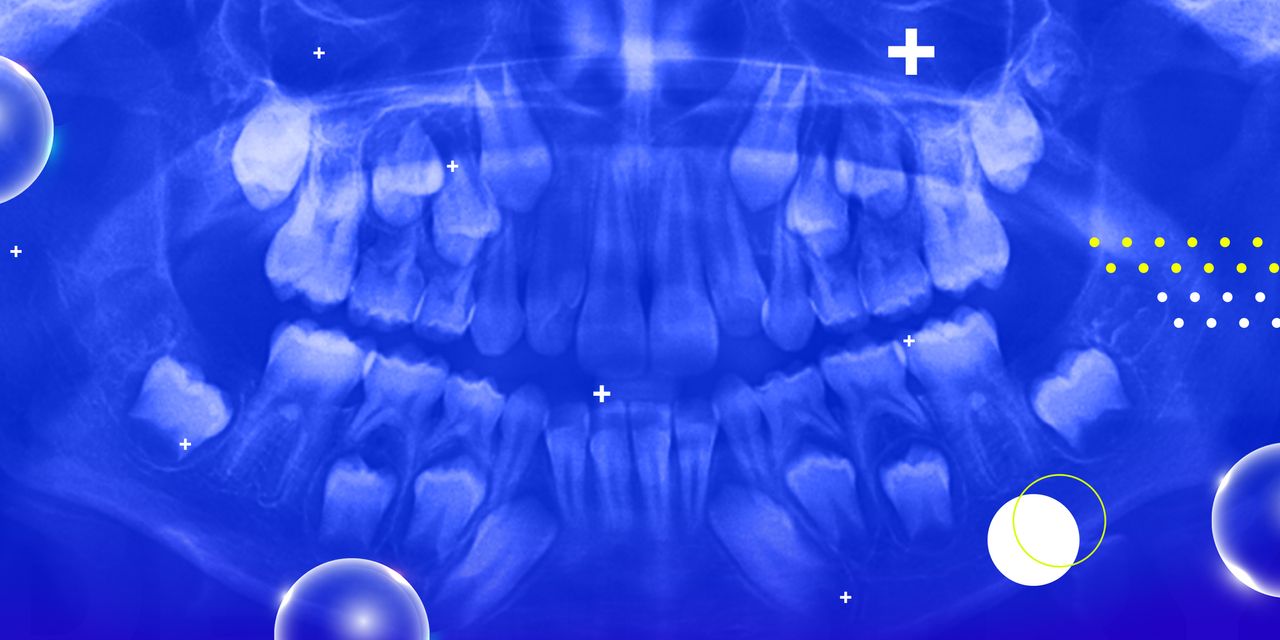

Oral Radiology: Benign and Malignant Lesions of the Jaws

This seminar will provide to the attendee the most common radiographic lesions that are presented in children and adults. The seminar will use case-presentation as the learning and discussion format and will cover the entire spectrum of oral radiology. Topics such as radiographic interpretation and common radiographic lesions will be covered in this seminar.

– Learn the most common radiographic lesions in infants, children and adults.